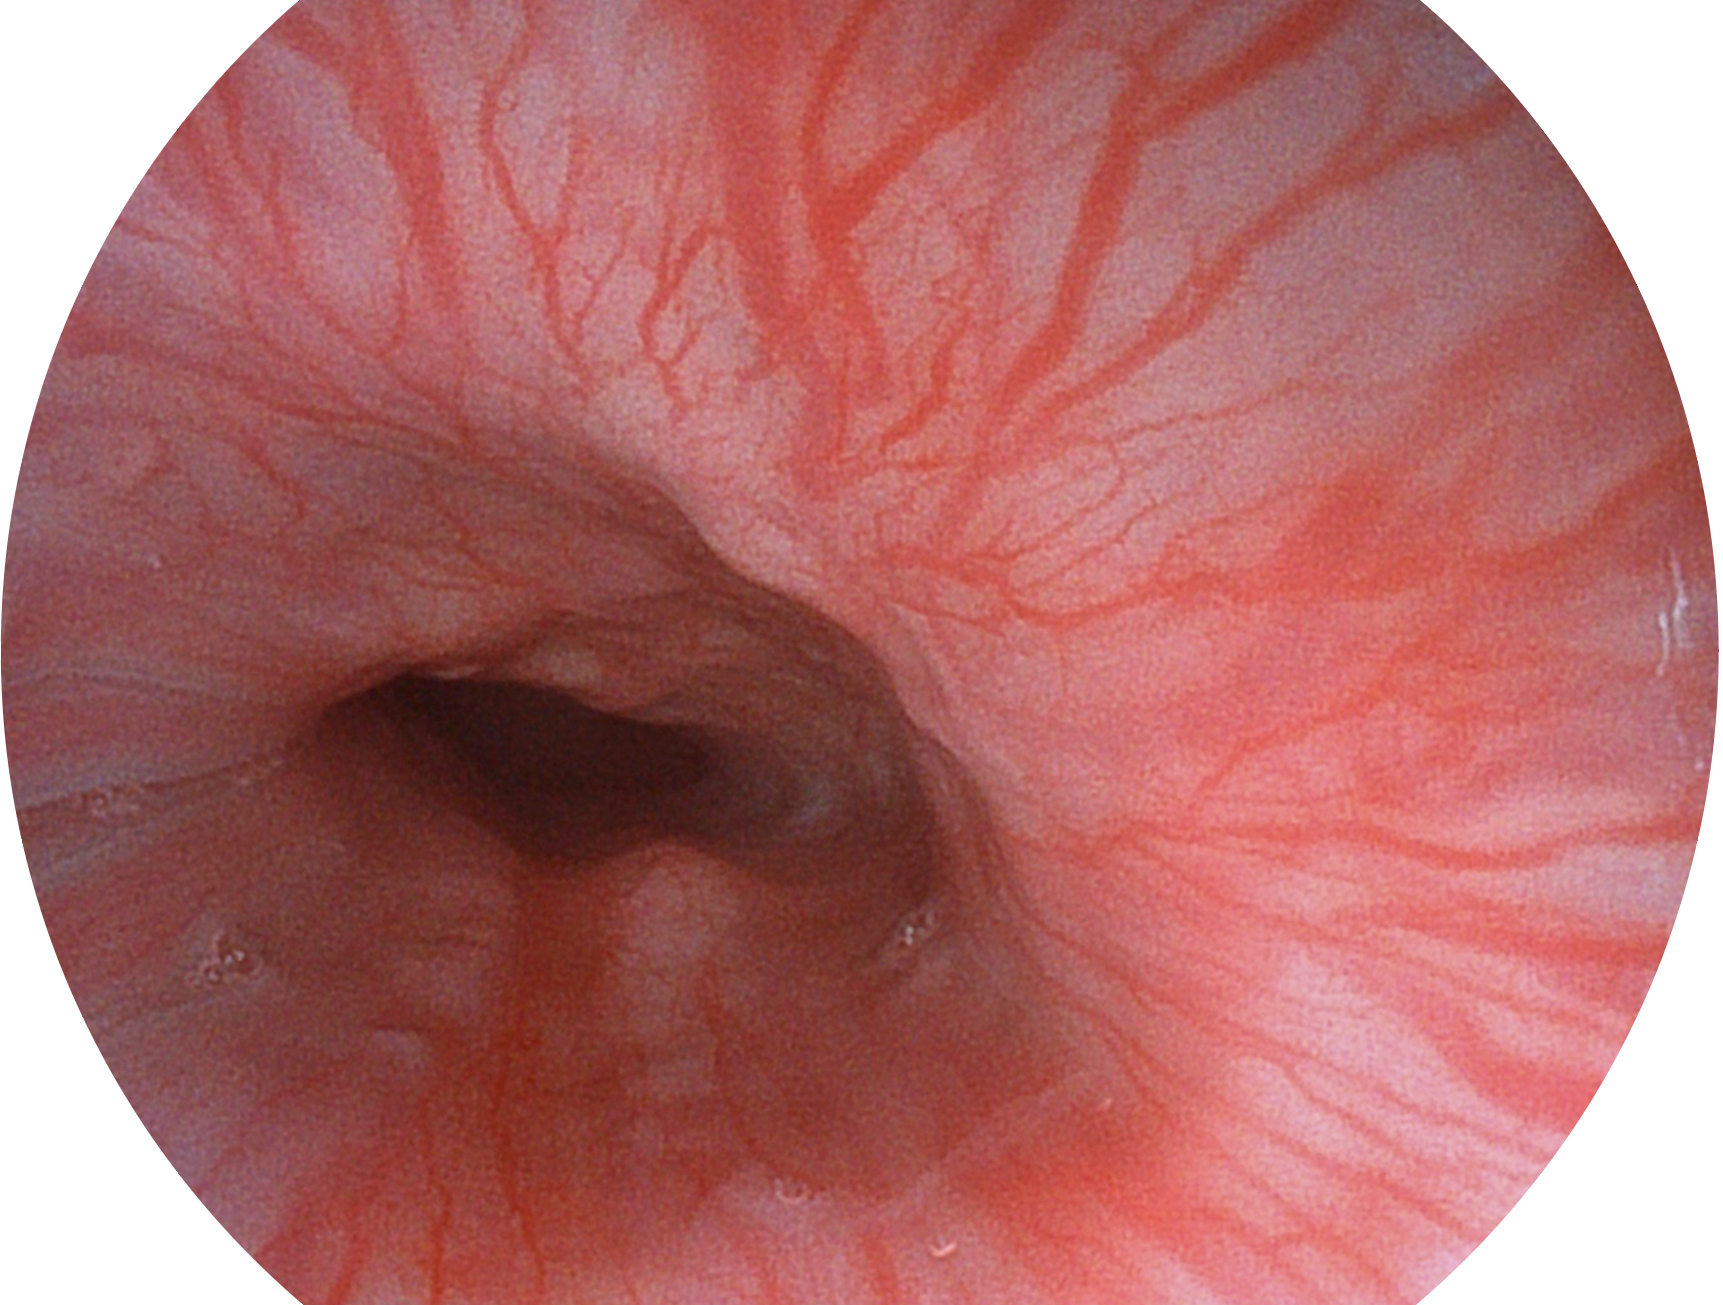

米兰官方网站新开发的内镜染色技术,主要是基于多波长LED 光源的开发,VLS-55Q 四波长LED 光源是由四个不同颜色的LED光按照相应照明模式所规定的特定发光比例进行合束后形成,合束后形成的照明光的光谱由红光、绿光、蓝光及蓝紫光这四个不同的波段范围构成。具有更高光谱自由度,通过光谱比例的控制,实现了聚谱成像技术,英文全称为“Spectral Focused Imaging, SFI”,缩写为“SFI”和光电复合染色成像技术,英文全称为“Versatile Intelligent Staining Technology, VIST”,缩写为“VIST”。